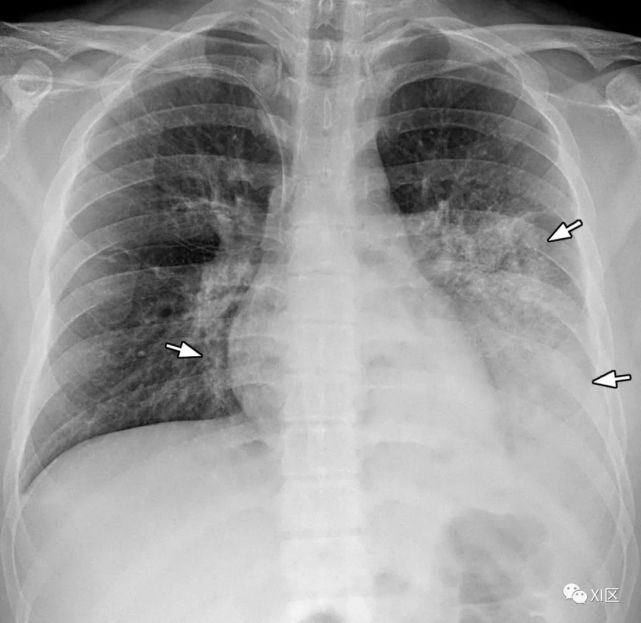

图16 58岁女性急性髓系白血病伴有发热,并发呼吸道合胞病毒肺炎。

(上) 初诊胸片显示双肺多发不规则结节状支气管周围气隙或GGO(箭头),少量双侧胸腔积液。在同一天在较低的气管水平(中)和叶间区水平(下)上获得的轴位胸部CT图像显示多个不规则的结节影和树芽征,沿支气管血管束斑片状实变,支气管壁轻度增厚。

Koo H J , Lim S , Choe J , et al. Radiographic and CT Features of Viral Pneumonia[J]. Radiographics, 2018, 38(3):719-739.